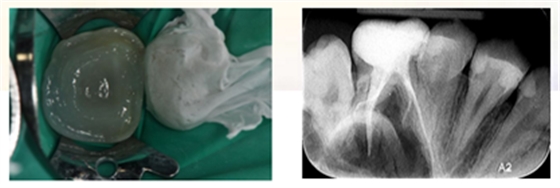

6、上橡皮障,去除近中龋坏组织,SDR树脂制作近中邻面假壁。

7、初步恢复牙体完整性后上橡皮障,开髓,3% NaClO冲洗,揭除髓顶,修整开髓洞形,去除髓腔牙髓组织。

8、定位根管口后,8#K锉结合根管冠方预敞,逐步探查,四根管通畅。因操作时间过长,未作根管预备,氢氧化钙糊剂暂封根管一周,玻璃离子暂封。